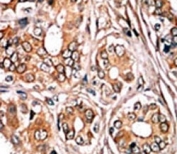

IHC analysis of FFPE human breast carcinoma tissue stained with the phospho-Rb antibody.

IHC (Paraffin) : 1:50-1:100